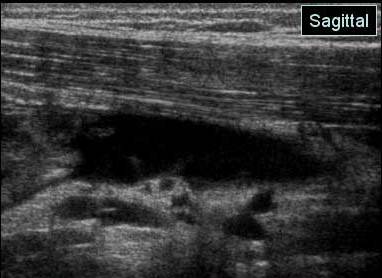

Echivalentul stadiului IV al lui Rodineau se caracterizeaza prin existenta unei rupturi sau unei dezinsertii musculo-aponevrotice complete cu,cel mai frecvent fascicol muscular retractat flotant intr-o cavitate hematica

Stadiul IV Rodineau – ruptura la jonctiune mio tendinoasa

Muschi retractat flotant in colectie hematica

Echivalentul stadiului IV al lui Rodineau se caracterizeaza prin existenta unei rupturi sau unei dezinsertii musculo-aponevrotice complete cu,cel mai frecvent fascicol muscular retractat flotant intr-o cavitate hematica Exista in aceste echivalente ale stadiului IV un caz particular, reprezentat de o ruptura osteotendinoasa (traumatismul spinei iliace antero-inferioare in leziunile dreptului femural la fotbalisti de exemplu